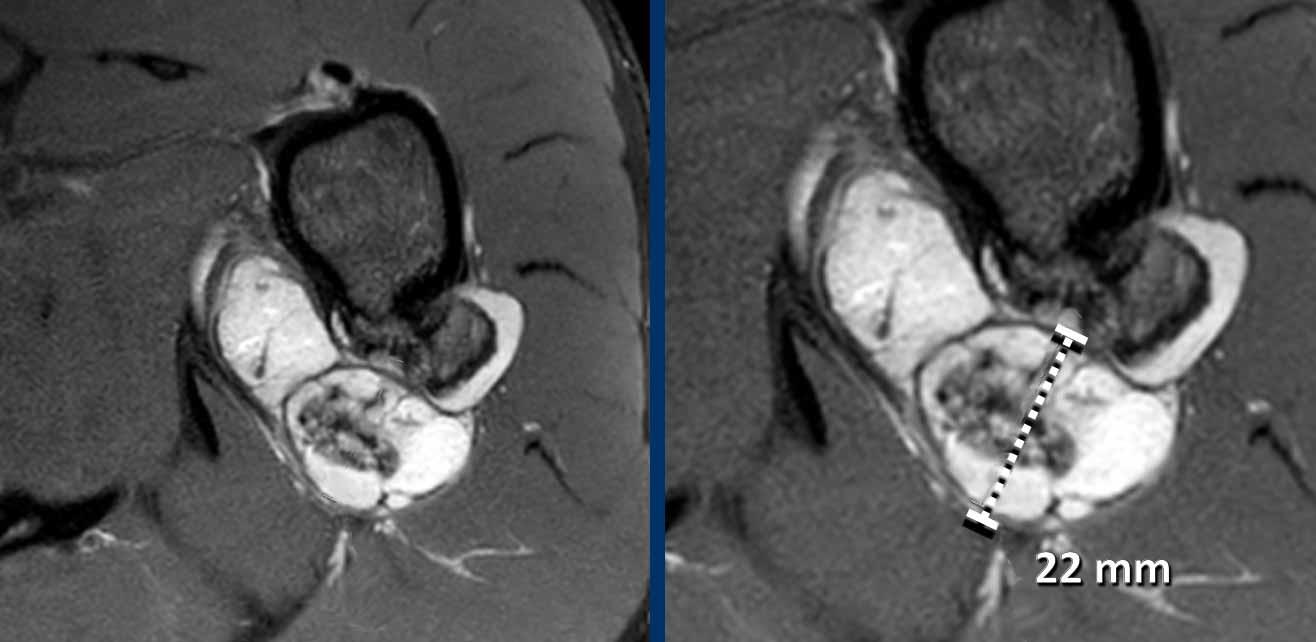

Hình ảnh

Hình ảnh T2W trục ngang có kỹ thuật ức chế mỡ cho thấy u xương sụn ở mặt sau đầu trên xương cánh tay trái với độ dày mũ sụn 22 mm.

Trong các tổn thương

có mũ sụn > 2 cm, phẫu thuật cắt bỏ được thực hiện để loại trừ

u sụn ác tính.

Khối u đã được cắt bỏ và

kết quả giải phẫu bệnh phù hợp với u vỏ thượng thận ngoại vi.